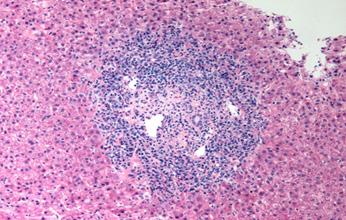

Biopsias de intestino delgado:

♦ detección de macrófagos espumosos con gránulos PAS + en la lámina propia ( ENARM 2020)

Figura 54. La triada clásica de la enfermedad de WHIPPLE es la presencia de diarrea, artritis y fiebre. (ENARM 2020) Figura 55. Macrófagos PAS positivos en el intestino delgado de un paciente no tratado con enfermedad de Whipple.